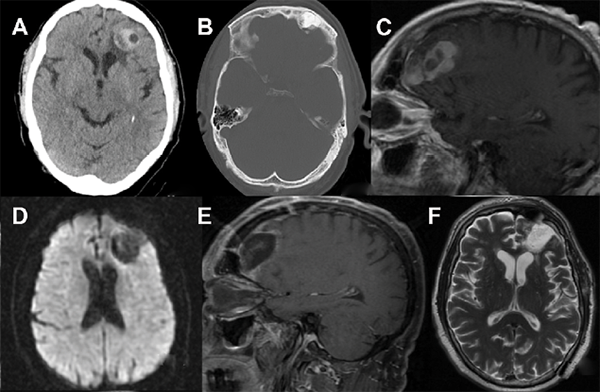

Se completó el estudio con una resonancia magnética (RM) cerebral con contraste y secuencias de difusión y mapa de coeficiente de difusión aparente (ADC) ante el diagnóstico diferencial planteado de absceso cerebral versus tumoración intracraneal. Se determinó una lesión exofítica en el seno frontal izquierdo de intensidad de señal compatible con tumoración ósea, así como la disrupción de la tabla interna en solución de continuidad con una masa de 30 X 28 X 32 mm, de bordes definidos, sin restricciones a la difusión ni inversión en secuencias de ADC y captación heterogénea de contraste. Dichos hallazgos plantearon el diagnóstico de osteoma frontal complicado con mucocele intracerebral. No se pudo descartar la presencia de proceso inflamatorio/infeccioso subyacente dado el artefacto de señal por presencia de calcio, colecciones hemáticas y su proximidad a la base del cráneo. Se consideró la posibilidad de un glioma de alto grado (Fig 1 A-D).

Fig 1. Estudio radiológico. A) TC cráneo-cerebral.Ventana de parénquima cerebral donde se observa lesión frontal hiperdensa heterogénea frontal izquierda B) TC cráneo-cerebral. Ventana de hueso: Osteoma frontal con discontinuidad en la pared posterior del seno frontal. C) RMN cerebral (T1) con contraste: captación heterogénea de la lesión en íntima relación con el seno frontal D) RMN cerebral (DWI): No se identifica restricción de difusión a nivel frontal. E) RMN cerebral de control postquirúrgica. Sagital (T1) con contraste: resección completa de lesión frontal. No se identifica captaciones anómalas. F) RMN cerebral de control postquirúrgica. Axial (T2).

El paciente fue dado de alta a las noventa y seis horas de su ingreso con cobertura antibiótica (amoxicilina-clavulánico 875-125mg/8h hasta completar los diez días de tratamiento) a pesar de la negatividad de los cultivos tomados intraoperatoriamente. En la actualidad, seis meses más tarde, el paciente se mantiene asintomático, sin secuelas neurológicas y en seguimiento clínico-radiológico por nuestra especialidad. Presentamos el primer control de resonancia magnética realizado un mes y medio tras la intervención en el que se aprecia resolución completa de la lesión (Fig 1 E-F).